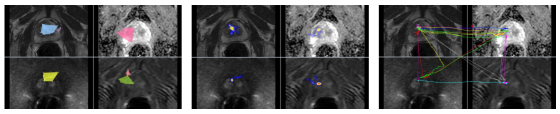

2.2 Step 1: A graph representation of the eye-tracking data

An example of eye-tracking data recorded from two cancer screening tasks is shown in Fig. 3 and Fig. 4. For each experiment, 2D images are overlaid with the coverage area (left), heatmap (middle), and scanpaths (right) representations inferred from the gaze patterns. Once gaze patterns are recorded, they are dense, hence, difficult to analyze (See Fig. 5). The aim in data sparsification is to represent the data with far less parameters and without significantly losing its content. It is also desirable to process the data easily and efficiently when sparisified. To end this, we propose to represent eye-tracking data as a graph and reduce its size without distorting the topology of the data structure by utilizing clustering and sparsification algorithms.

This experiment was performed on a multi-parametric MRI scan of a single subject. MRI characteristics are: axial T2 weighted (T2w), with FOV of and resolution of , Dynamic Contrast Enhanced (DCE) with FOV of and resolution of , , Diffusion Weighted Imaging (DWI) with FOV of and resolution of . Apparent Diffusion Coefficient (ADC) map was derived from 5 evenly spaced b value () DWI.

One of our participating radiologists, an expert in prostate cancer screening, examined multi-parametric MRI (four 3D images) for routine prostate cancer screening. Based on the results reported in Fig. 16, it is evident by the sparsified graphs that the radiologist used axial T2-weighted images (anatomical information) and ADC maps (showing magnitude of diffusion) more frequently than other two images. This observation suggests that although all four modalities are being used for making a diagnostic decision T2-weighted and ADC map are more informative to the radiologists in the screening process. This observation can be useful in further developments of automatic computer-aided diagnosis systems.